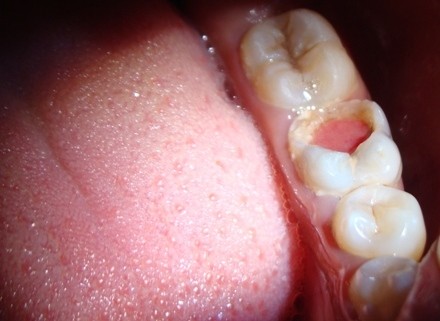

Reversible and irreversible pulpitis

Inside the innermost part of each tooth is an area called the pulp. And Pulpitis is inflammation of the dental pulp, or tissue in the center of a tooth. The dental pulp comprises soft connective tissue, nerves, and the blood supply for the tooth.

There are two forms of pulpitis: reversible and irreversible.

Reversible pulpitis refers to instances where the inflammation is mild and the tooth pulp remains healthy enough to save. Irreversible pulpitis occurs when inflammation and other symptoms, such as pain, are severe, and the pulp cannot be saved.

The most common cause of pulpitis is when bacteria irritate the dental pulp through an area of tooth decay, including dental caries.

Other causes of pulpal inflammation include: trauma or injury to a tooth, grinding or clenching the teeth repeated, invasive dental procedures.

These irritants typically first cause reversible pulpitis. If the pulp continues to be inflamed, the pulpitis becomes irreversible, which may eventually lead to the pulp dying.